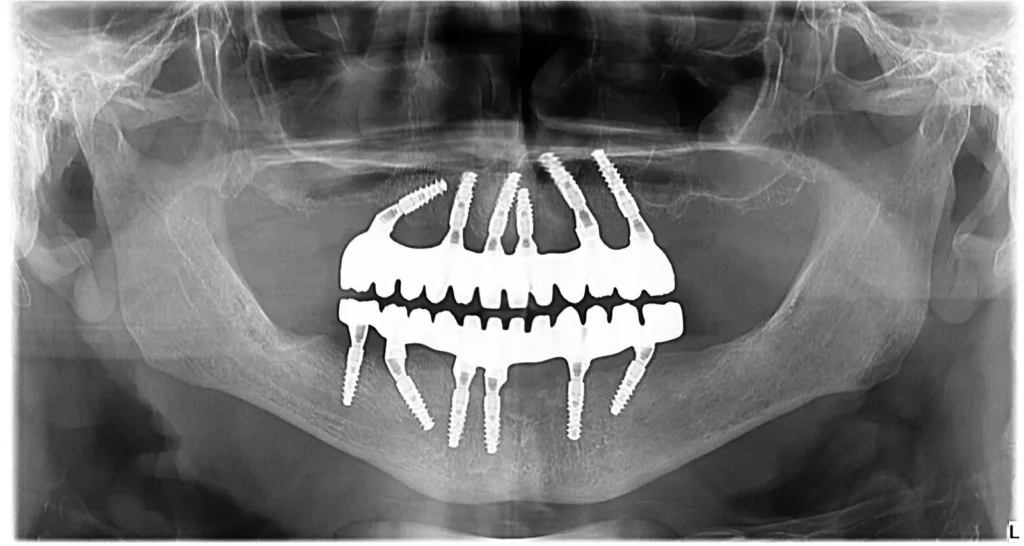

Am recomandat extracția dinților irecuperabili, all on 6 la maxilar și all on 6 la mandibulă.

• Am efectuat o reabilitare completa prin inserarea a 6 implanturi la maxilar si 6 implanturi la mandibula. In 24 de ore, a primit doua lucrări provizorii fixe, care a asigurat functionalitate si estetica imediata.

• Dupa o perioada de 6 luni de osteointegrare, s-au realizat lucrarile definitive din ceramica stratificata pe zirconiu, atat la maxilar, cat si la mandibula. Rezultatul final a restabilit ocluzia, un zambet natural.